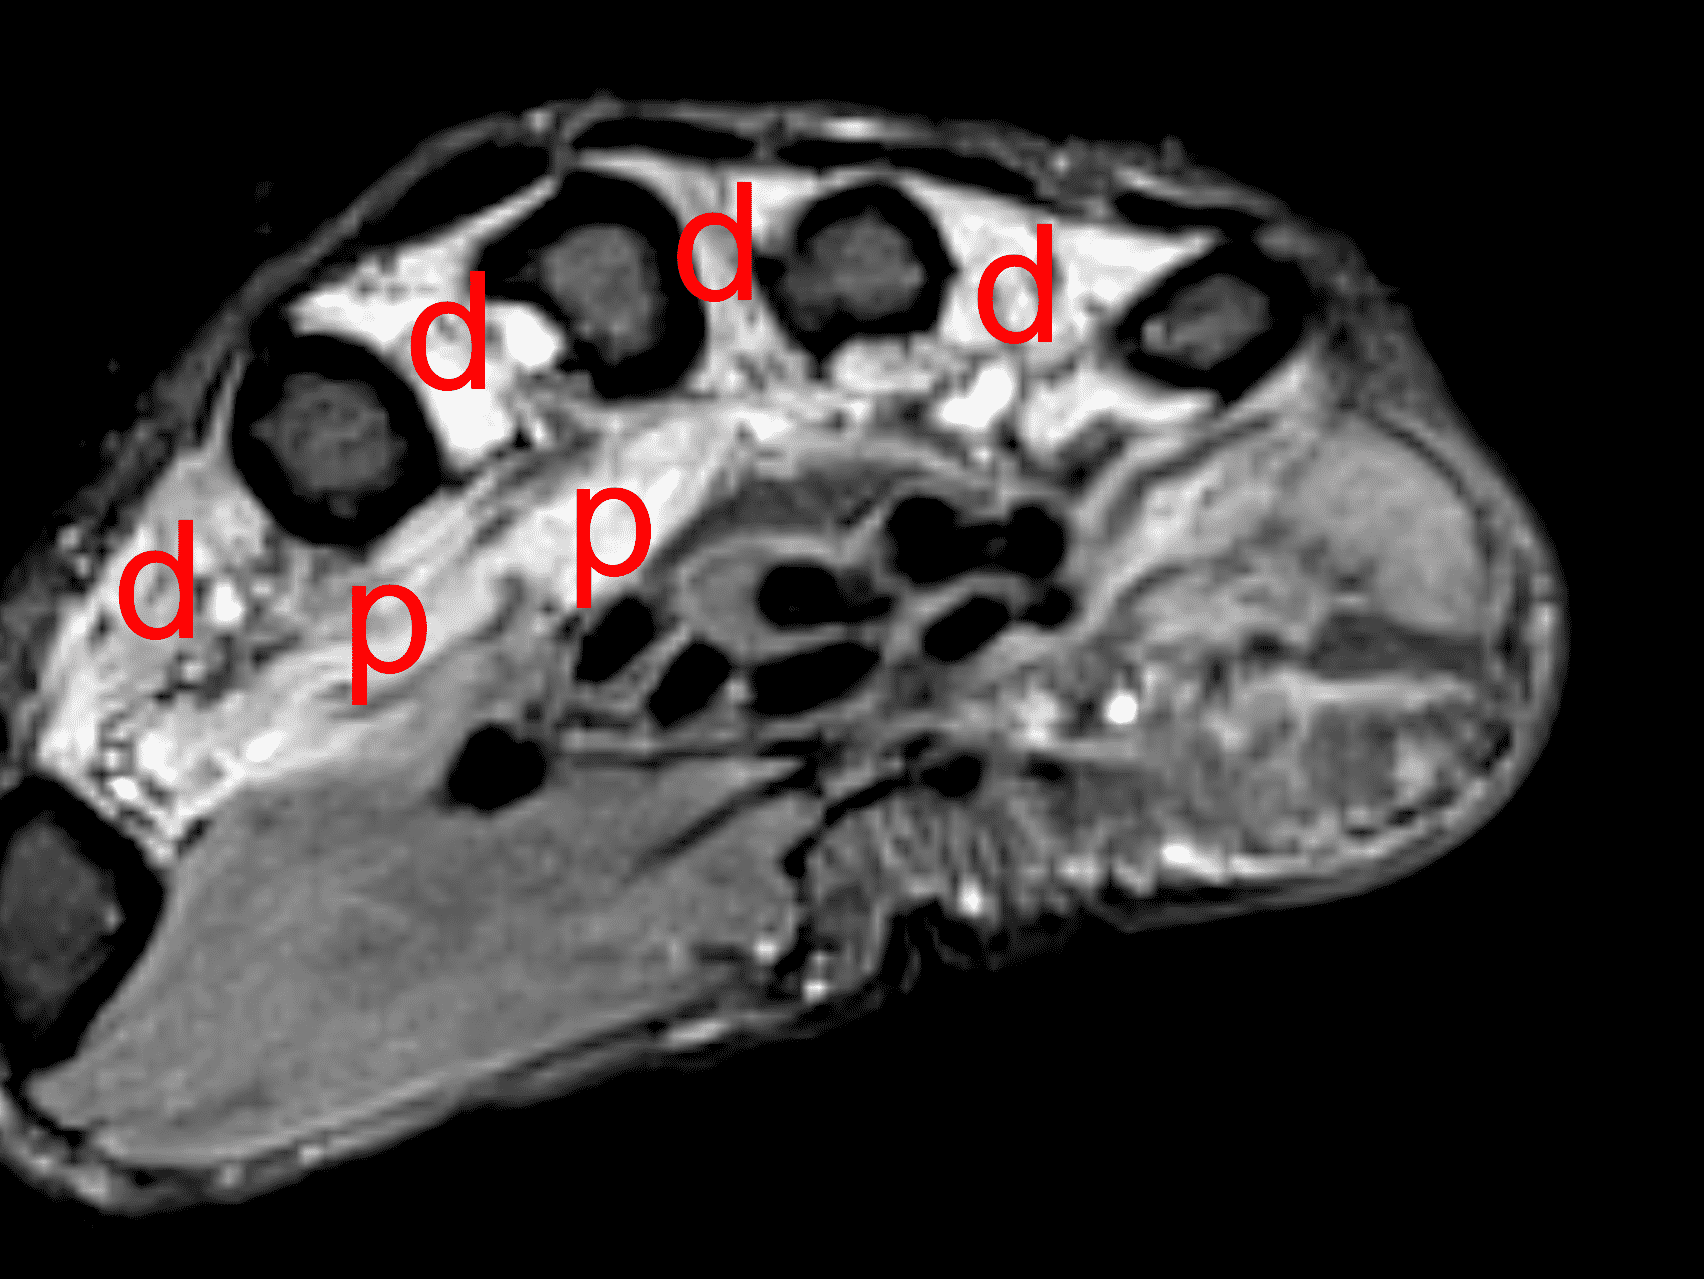

Figure 16: Ulnar neuritis with muscle denervation. In addition to sensory symptoms, this woman also presented with decreased grip strength. (16A) Axial STIR image through the proximal palm shows high signal intensity within the dorsal (d) and palmar (p) interosseous muscles, representing subacute denervation in the ulnar nerve distribution. (16B) A STIR image slightly more distally also shows subacute denervation involving the adductor pollicis (adp), opponens digiti minimi (o), abductor digiti minimi (ab), and third and fourth lumbrical (arrows) muscles. Despite having no symptoms at the elbow, nerve conduction studies and EMG confirmed ulnar nerve dysfunction at the cubital tunnel.